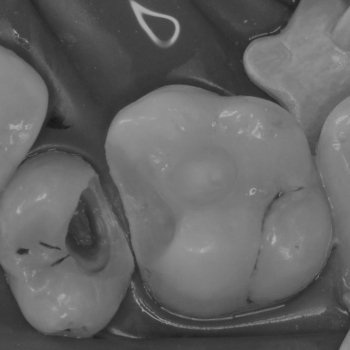

Вместо удаления сохранение зуба

Лечение и результат